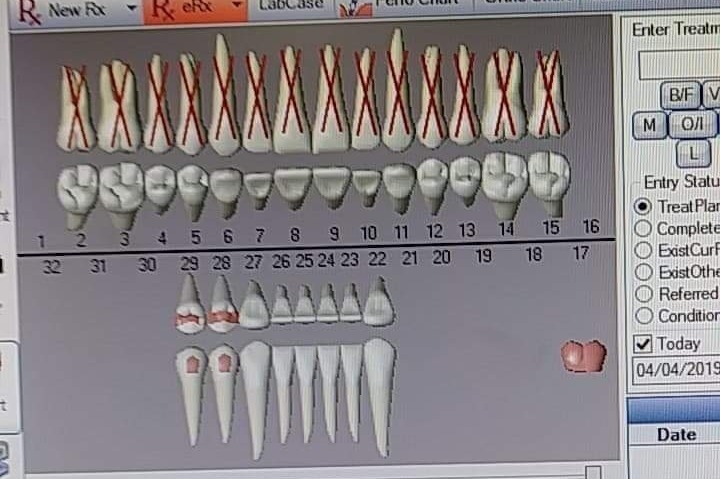

I need all my top teeth removed its covered. I need bonegrafting and healing dentures that is not. With 6 kids I cant pull funds from bills or their needs to do this. If I could have done it at a younger age I would have. Now I have time just not the money. if you can help thank you so much. Please no ride or negative comments. Ive been trying to get this done for many years. Ive been consumed by life completely and now I just need it done